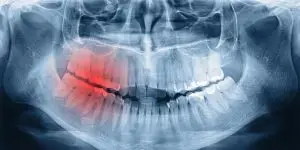

If you suspect you may have broken your jaw, you may wonder whether you need to be seen by a doctor or a dentist, and how serious it is. Both doctors and dentists can treat you. If you experience trouble breathing or your tongue swells, seek treatment from a medical doctor immediately. A broken jaw is a dental emergency and should be treated as such. Here’s what you need to know if you break your jaw.

Why Are Broken Jaws So Serious?A broken jaw is a serious dental emergency because of the potential impact on the alignment of your teeth, or your dental bite. If the bone is left to heal on its own and your bite is off, this can affect your ability to chew, how straight your teeth are, and the overall health and well-being of your teeth both now and into the future. Treating a bite that is misaligned is much harder once the jaw bone heals. This is why you should seek Mesa emergency dentistry services early on.